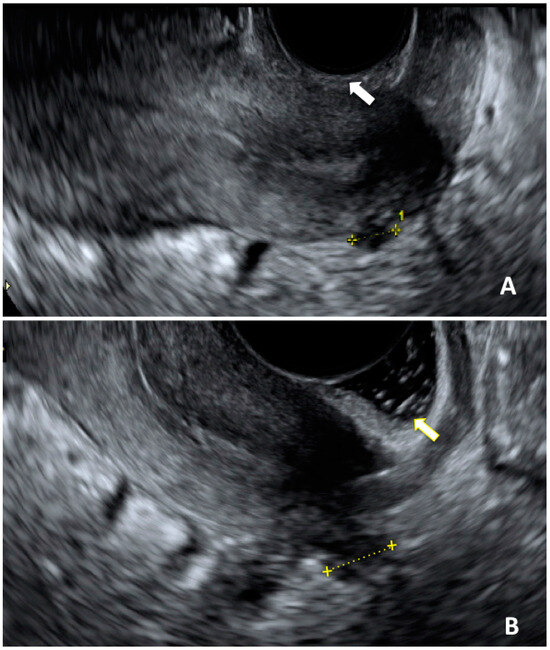

- Martire, F.G.; Lazzeri, L.; Conway, F.; Siciliano, T.; Pietropolli, A.; Piccione, E.; Solima, E.; Centini, G.; Zupi, E.; Exacoustos, C. Adolescence and endometriosis: Symptoms, ultrasound signs and early diagnosis. Fertil. Steril. 2020, 114, 1049–1057. [Google Scholar] [CrossRef]

- Martire, F.G.; Russo, C.; Selntigia, A.; Nocita, E.; Soreca, G.; Lazzeri, L.; Zupi, E.; Exacoustos, C. Early noninvasive diagnosis of endometriosis: Dysmenorrhea and specific ultrasound findings are important indicators in young women. Fertil. Steril. 2023, 119, 455–464. [Google Scholar] [CrossRef]

- Hudelist, G.; Ballard, K.; English, J.; Wright, J.; Banerjee, S.; Mastoroudes, H.; Thomas, A.; Singer, C.F.; Keckstein, J. Transvaginal sonography vs. clinical examination in the preoperative diagnosis of deep infiltrating endometriosis. Ultrasound Obstet. Gynecol. 2011, 37, 480–487. [Google Scholar] [CrossRef]

- Exacoustos, C.; Lazzeri, L.; Martire, F.G.; Russo, C.; Martone, S.; Centini, G.; Piccione, E.; Zupi, E. Ultrasound Findings of Adenomyosis in Adolescents: Type and Grade of the Disease. J. Minim. Invasive Gynecol. 2022, 29, 291–299.e1. [Google Scholar] [CrossRef]